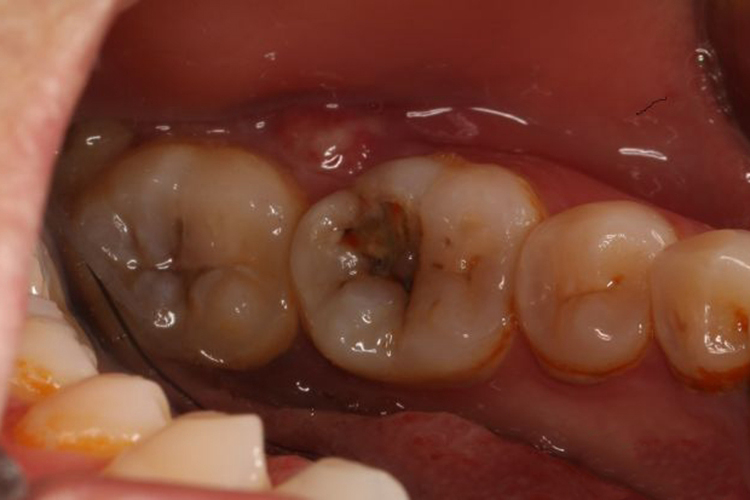

慢性根尖周炎

一般无自觉症状,患牙在咀嚼时可有不适感,也可伴有牙髓肿痛。

慢性根尖周炎:首选根管治疗。较大的根尖病变,尤其是根尖周囊肿患牙,在根管治疗的基础上有时还需做根尖手术。根管治疗后,择期进行牙冠的修复,可根据剩余牙体组织的量选择复合树脂直接粘接修复,嵌体修复,或全冠、桩核冠修复。严重的患牙,应予以拔除。